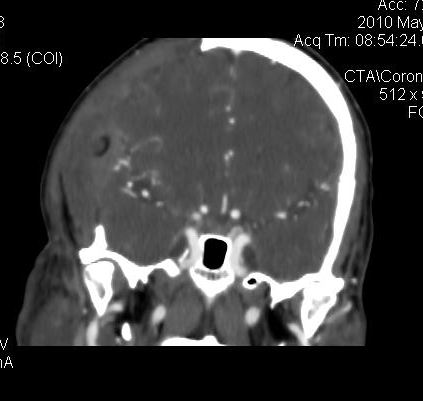

男.60岁,渐进性意识不清,ct检查双侧额颞顶部硬膜下血肿,开颅术后行脑血管cta,大脑中动脉起始部见一瘤状血管扩张。请各位老师留下宝贵意见

太常见了,报动脉瘤就可以

符合动脉瘤表现。

符合动脉瘤表现。

动脉瘤。

颅内动脉瘤。

后重建做得不是很好看,要将维蒂斯环充分显示,最好在增加一个mip。这样不好定位。

小动脉瘤

典型

符合动脉瘤的表现

动脉瘤

符合动脉瘤表现。

小动脉瘤

典型